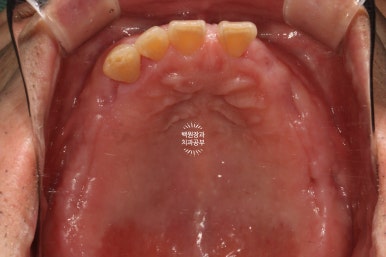

구강내 교합면 사진입니다.

파노라마 엑스레이상에서 많은 치아가 있어보이지만,

실제로 대부분의 치아는 많은 양의 치석이 침착되어 만성치주염의 주소견인 흔들림을 보여주고 있었습니다.